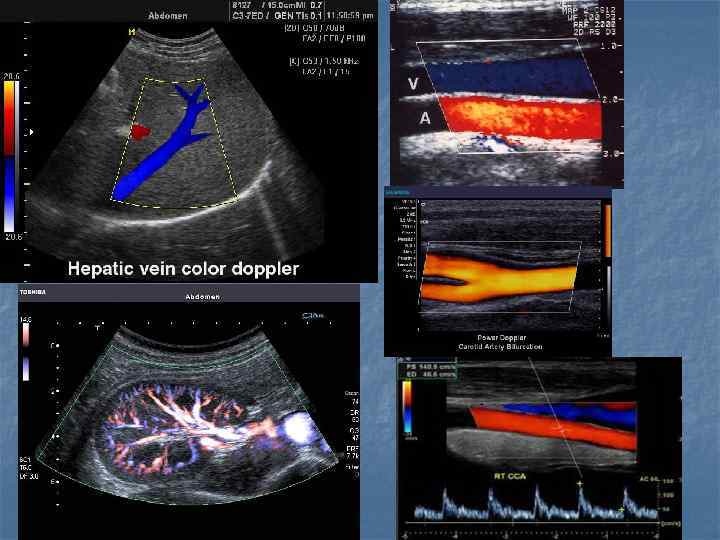

Показания n n n n Воспалительные заболевания брюшной полости, малого таза и шеи… Наличие жидкости в брюшной и грудной полостях, в суставах Визуализация мягких тканей(мышцы, связки, околосуставные пространства) Желчекаменная, почечнокаменная болезни Диагностика опухолей (молочная железа, яичники, лимфоузлы) Заболевания сосудов(варикозная болезнь, эндортереит, оартиты, аневризмы, ангиопатия) Врожденные и воспалительные заболевания сердца(пороки клапанного аппарата, дефекты стенок, нарушение функции миокарда, эндокардит, перикардит)